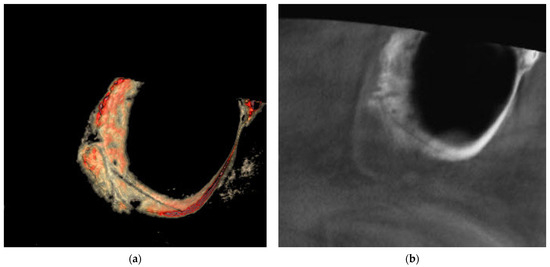

The aim of this study is to evaluate anatomical considerations and assess the volume of the maxillary sinus bone graft. There were sixty-three patients (eighty-three sinuses) who had taken CT scans for implant surgery. Patients included those whose height of the residual alveolar [...] Read more.

The aim of this study is to evaluate anatomical considerations and assess the volume of the maxillary sinus bone graft. There were sixty-three patients (eighty-three sinuses) who had taken CT scans for implant surgery. Patients included those whose height of the residual alveolar bone was less than 5 mm. The position of posterior superior alveolar artery, the thickness of the maxillary sinus wall, and the volume of the maxillary sinus according to the amount of sinus floor elevation were measured. The mean vertical distance of posterior superior alveolar artery was 11.91 ± 4.79 mm from 3.03 mm to 24.05 mm. The mean thickness of the lateral wall was 1.71 ± 0.55 mm in the range of 0.74 mm to 3.93 mm. The volume of 3 mm, 5 mm, 7 mm, and 10 mm from the sinus floor was 0.173 ± 0.11 cm3, 0.526 ± 0.25 cm3, 1.068 ± 0.43 cm3, and 2.184 ± 0.74 cm3 on average, respectively. The knowledge of the posterior superior alveolar artery position, the lateral wall thickness, and the volume of the maxillary sinus can help the clinician for sinus bone graft. Full article